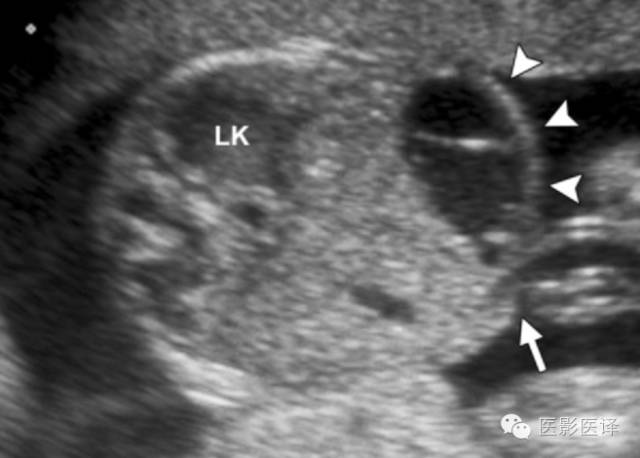

超声检查中,复杂性卵巢囊肿是厚壁的,且回声不均质。图像特征包括多个分隔(图4、5)、内部移动性高回声、实性表现(图6),或液液平面(图5、7)。复杂性囊肿被认为是扭转的结果,胎儿比新生儿更常发生。出现复杂性囊肿的表现高度提示需要手术。与胎儿卵巢囊肿伴发的其他影像表现包括羊水过多和腹水,可能是由于漏出或囊肿破裂所致。肠管或肾脏的继发梗阻被认为是扭转时卵巢坏死引起的粘连所致。

图7 囊肿中的液液平面。(a)轴位胎儿超声图像显示在左肾(LK)前方一个孤立性囊性肿块(箭),脊柱(Sp)另一侧可以看到正常的右肾(RK),三周后的随访图像(未展示)显示团块中出现液液平面。(b)新生儿经腹长轴位图像显示一个薄壁囊性团块,有液液平面(箭),子囊(箭头)是卵巢囊肿的确诊征象。(c)新生儿矢状位T2WI显示一个出血性卵巢囊肿,有液液平面(箭)和低信号血液成分。